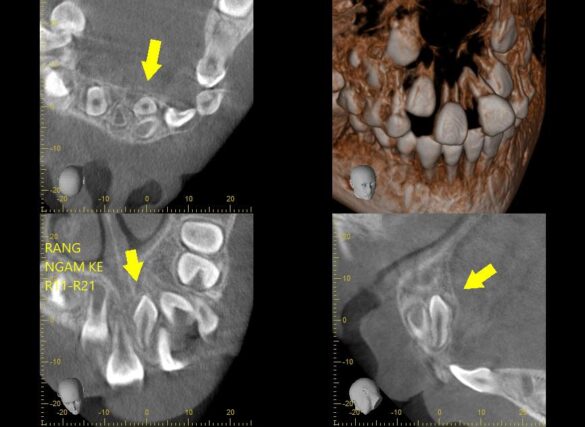

BN đến với than phiền từ bố mẹ rằng hai răng cửa vĩnh viễn của con mọc lên mỗi bạn xoè ra một hướng khác nhau ko ai chịu gặp ai.

Nếu nguyên nhân chỉ là phanh môi bám thấp thì phương án giải quyết lại nhẹ nhàng hơn hẳn. Nhưng ẩn sâu sau màn mưa mà mắt thường không thể nhìn thấy là một bạn răng thừa ngầm mọc lộn ngược giữa kẽ hai răng 11 và 21 làm tách đôi chúng ra. Và nếu không chẩn đoán đúng thì dù có đưa phanh môi về vị trí bám đúng thì chúng mãi mãi cũng vẫn chưa thể gặp nhau được.

Điều đáng nói ở đây là sự quan tâm của bố mẹ đã phát hiện sớm vấn đề của con trước khi nó quá trầm trọng. Sự dũng cảm, hợp tác và hiểu chuyện của một cô bé 7 tuổi làm bác sĩ quá sức bất ngờ.

Thương con gái, lo lắng con bị đau sau quá trình hậu phẫu. Nhưng cuối cùng thì hai bác cháu ta đã chiến thắng bạn răng xấu xí để lớn còn đi thi hoa hậu con gái nhỉ 👍🏻👍🏻👍🏻👍🏻💙👧🏻